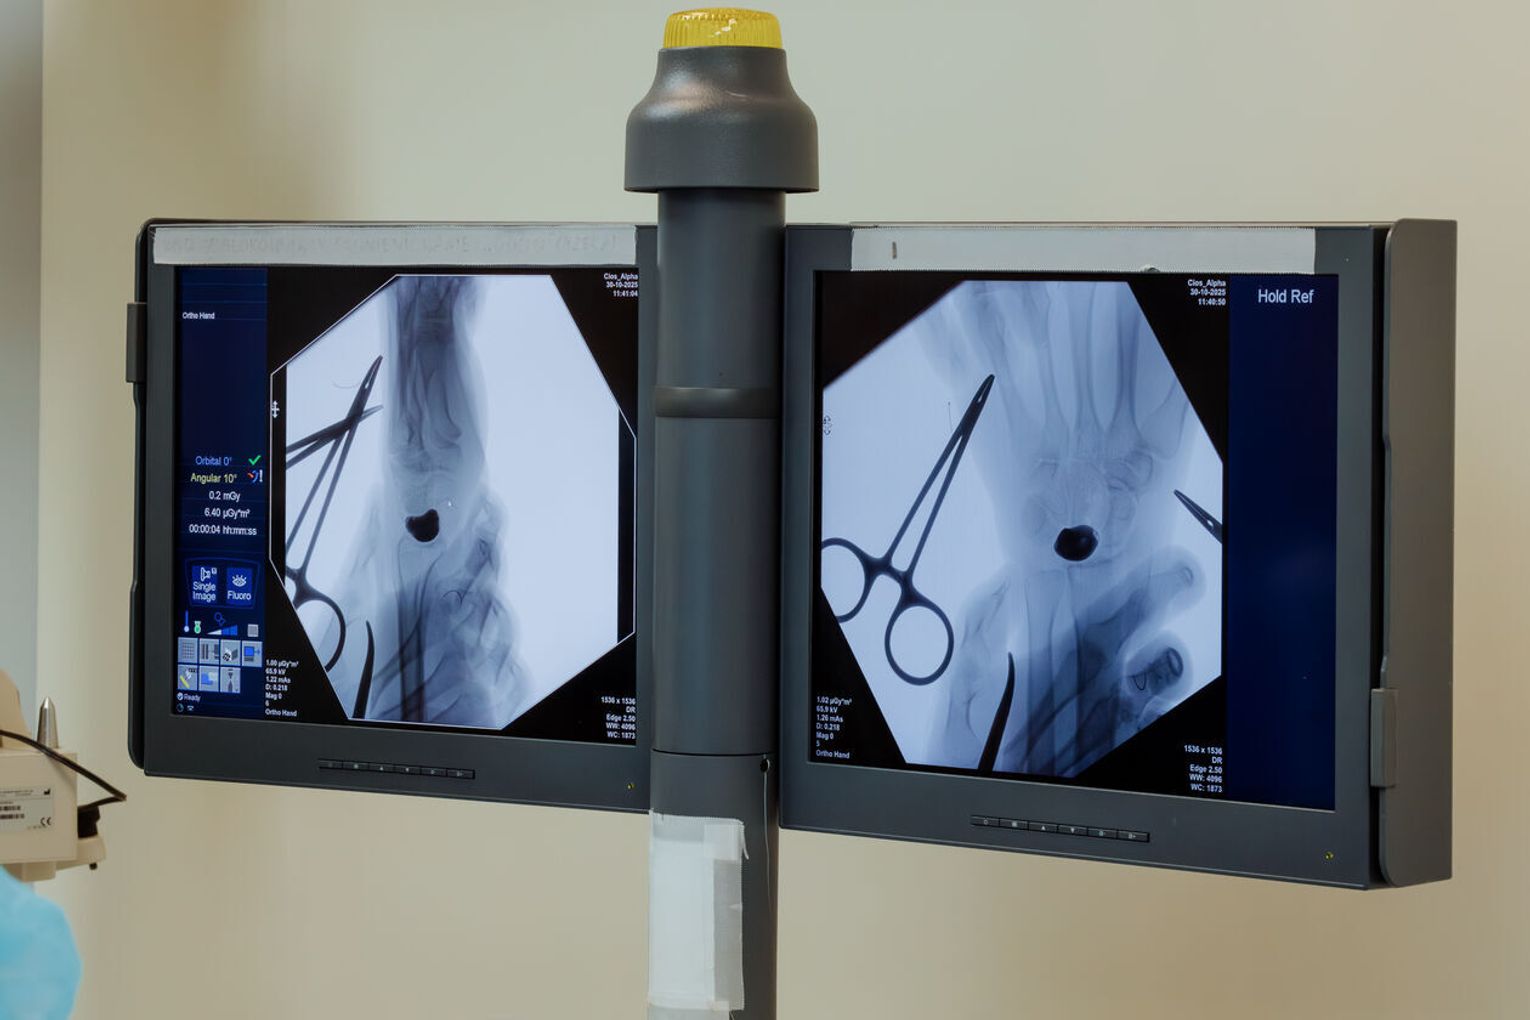

Przygotowania do operacji trwały rok. Lekarze wykonali cyfrowy model nadgarstka, na podstawie którego powstał implant z biokompatybilnego stopu tytanu. Powierzchnie odpowiedzialne za ruch i kontakt ze stawem wygładzono lub pokryto powłoką diamentopodobną, aby zminimalizować tarcie.

Zabieg przeprowadził zespół pod kierownictwem dr. n. med. Piotra Piecha.